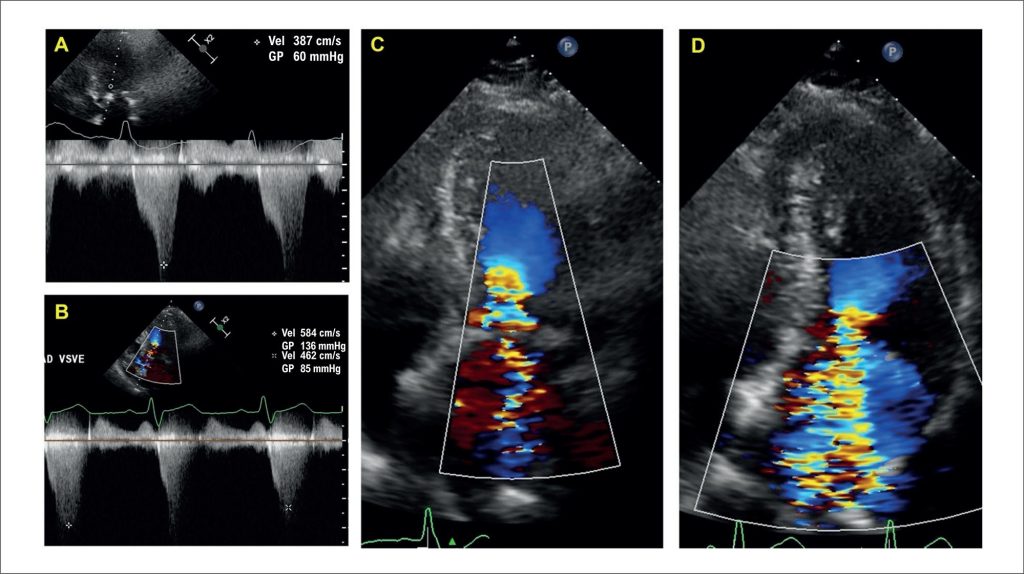

Tips and Pitfalls on the Role of Echocardiography in Percutaneous Intervention for Hypertrophic Cardiomyopathy

Hypertrophic cardiomyopathy (HCM) is the most prevalent genetic heart disease, affecting approximately 1 in 500 individuals in the general population,– with asymmetric septal hypertrophy as the most common phenotype. In obstructive HCM (oHCM), clinical relevance is greater due to its association with atrial fibrillation, heart failure, thromboembolic events, arrhythmias, and sudden cardiac death., For patients who remain symptomatic despite optimized medical therapy, septal reduction has become an established strategy, with surgical septal myectomy as the gold standard. Alcohol septal ablation is an alternative when surgical risk is prohibitive, there are contraindications to surgery, advanced age, or favorable coronary anatomy; it should be performed in experienced centers.– Other percutaneous approaches — such as radiofrequency septal ablation, the use of coils, or liquid embolic agents — have also been described.

Echocardiography plays a central role throughout the management of oHCM undergoing percutaneous intervention. Beyond diagnosis, it is essential for periprocedural guidance and for postoperative assessment. Understanding its capabilities and recognizing potential pitfalls are critical to success. This editorial offers practical tips for echocardiographers and highlights key points that, if overlooked, may compromise outcomes.